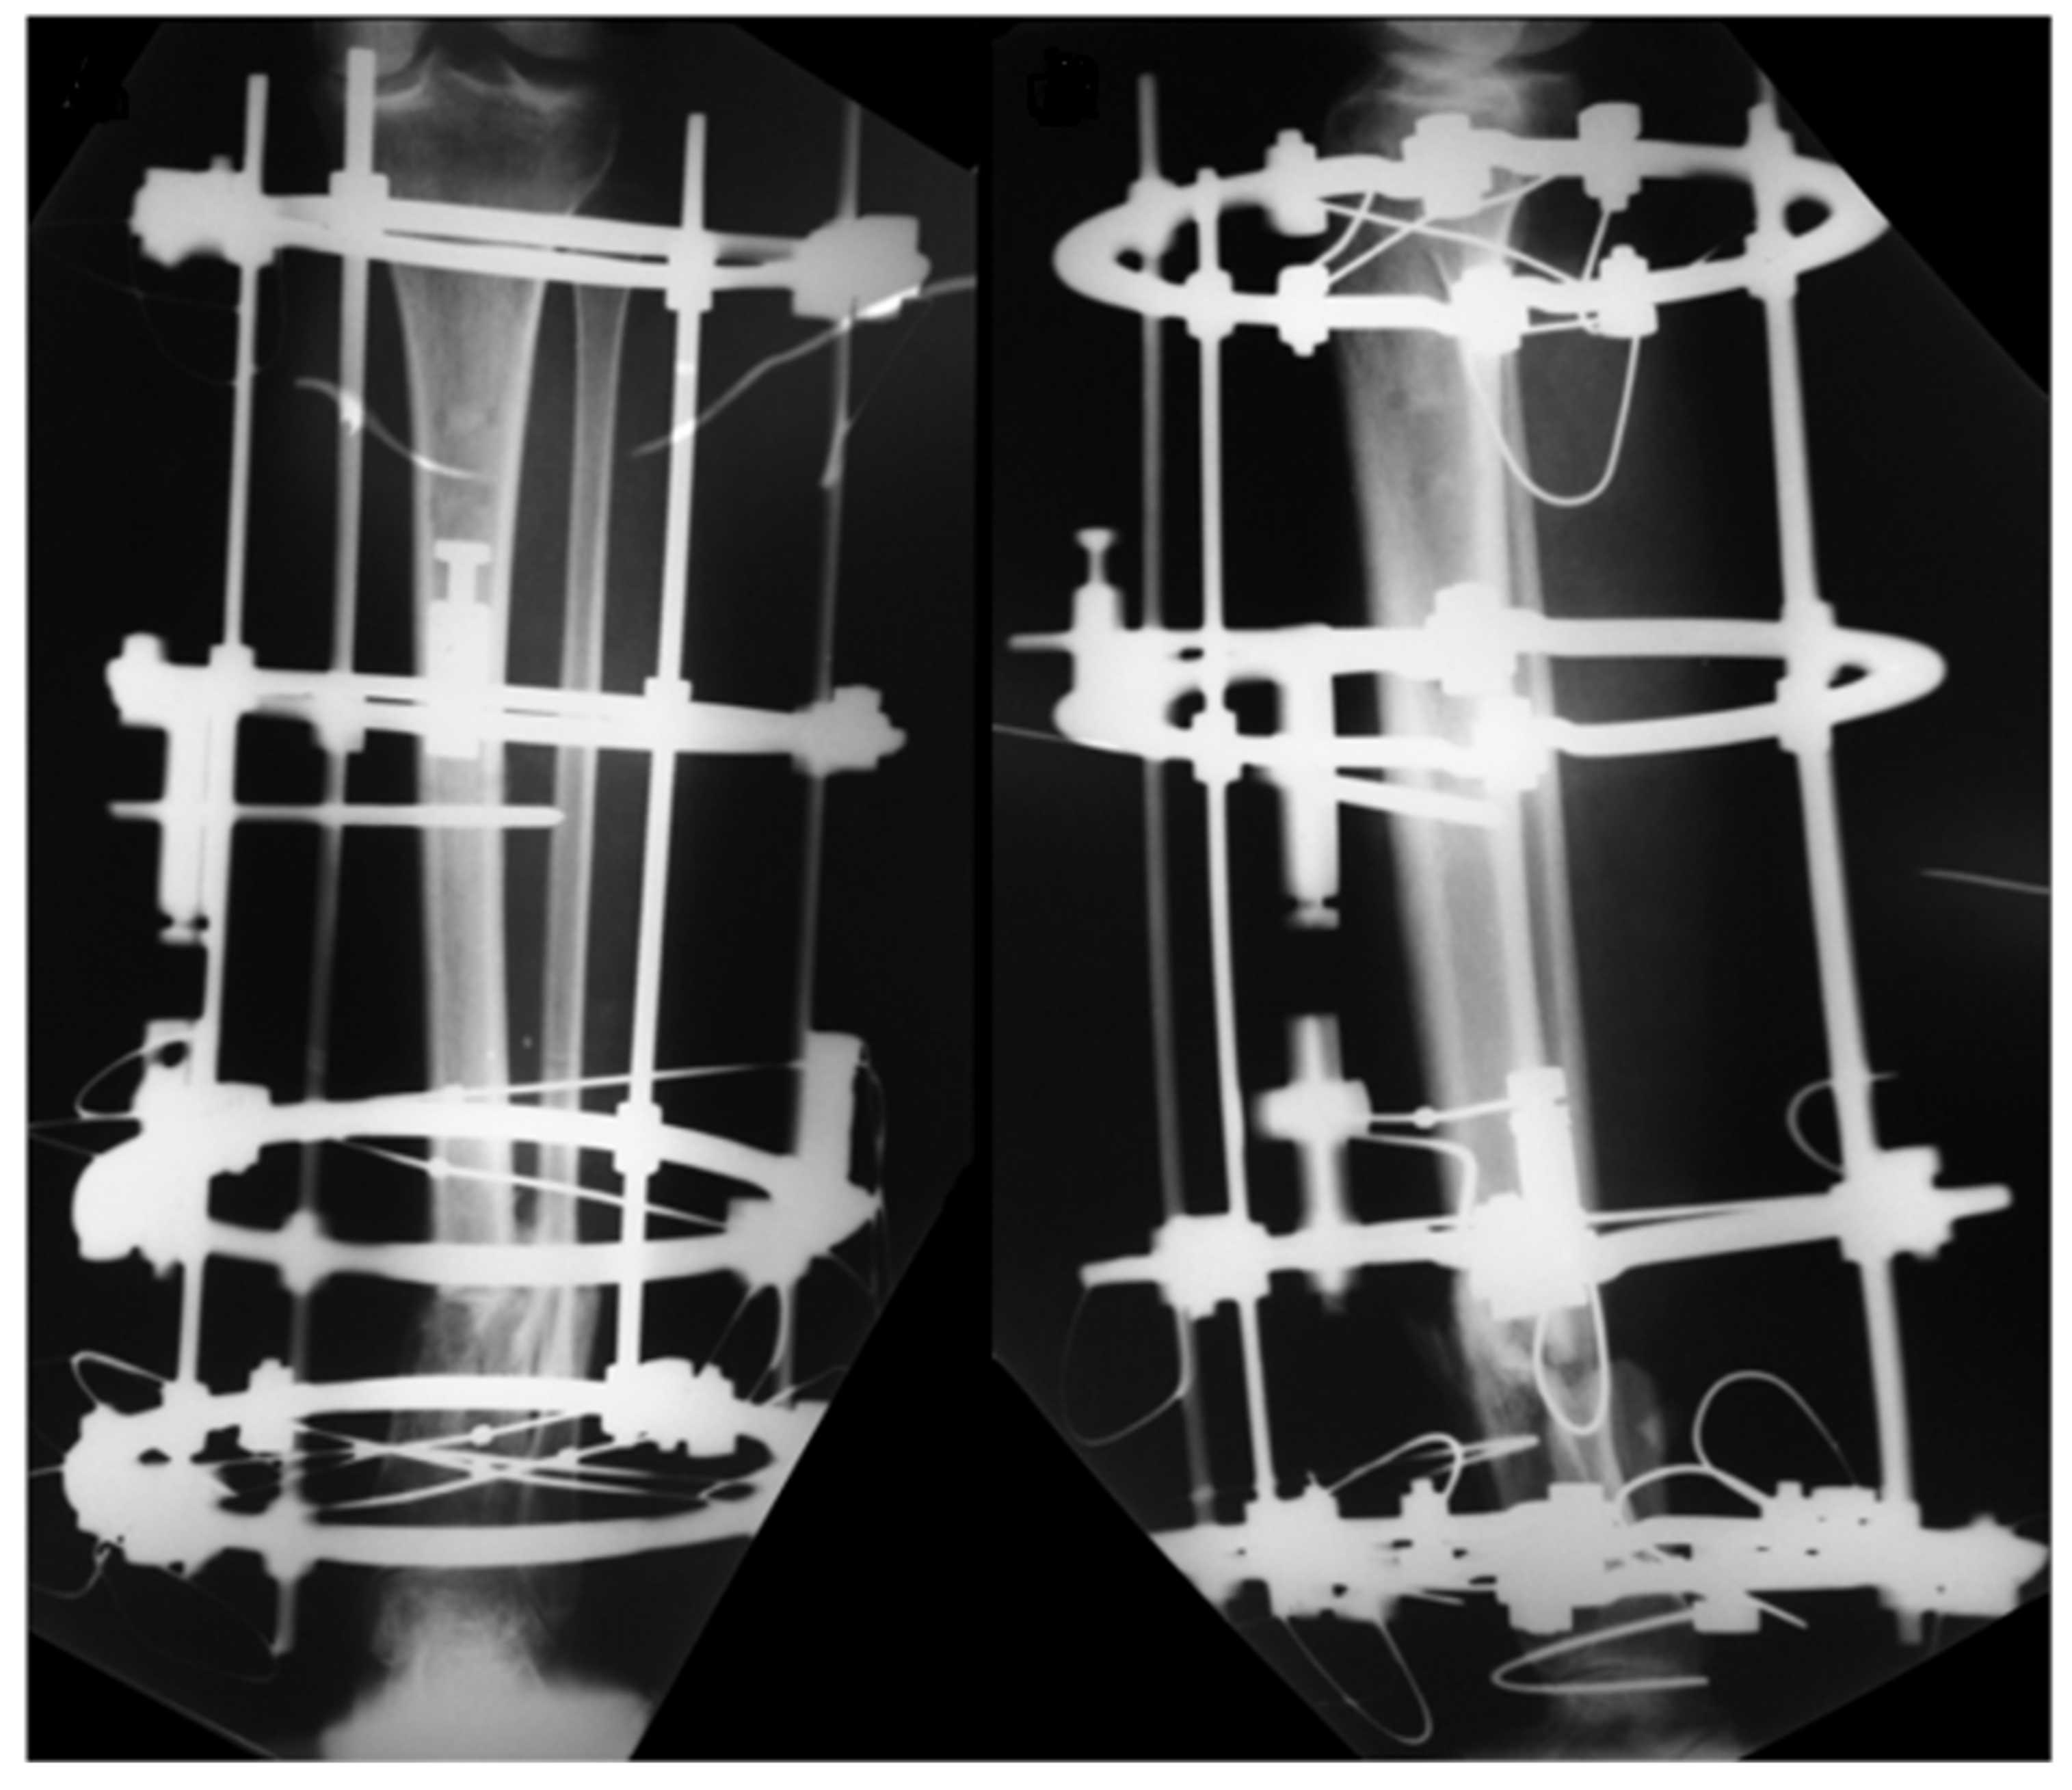

2. Case Report